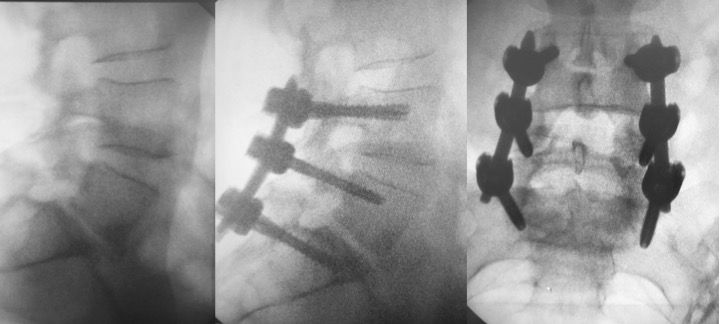

- nel trattamento delle instabilità del rachide (spondilolistesi congenite o degenerative) mediante interventi di stabilizzazione mininvasiva percutanea con barre e viti , barre e viti cementate, tlif, plif, xlif, artrodesi delle faccette articolari.

-TRATTAMENTOINSTABILITA’ DEL RACHDE

Stabilizzazione barre e viti percutanea

Artrodesi percutanea (tlif, plif, xlif)